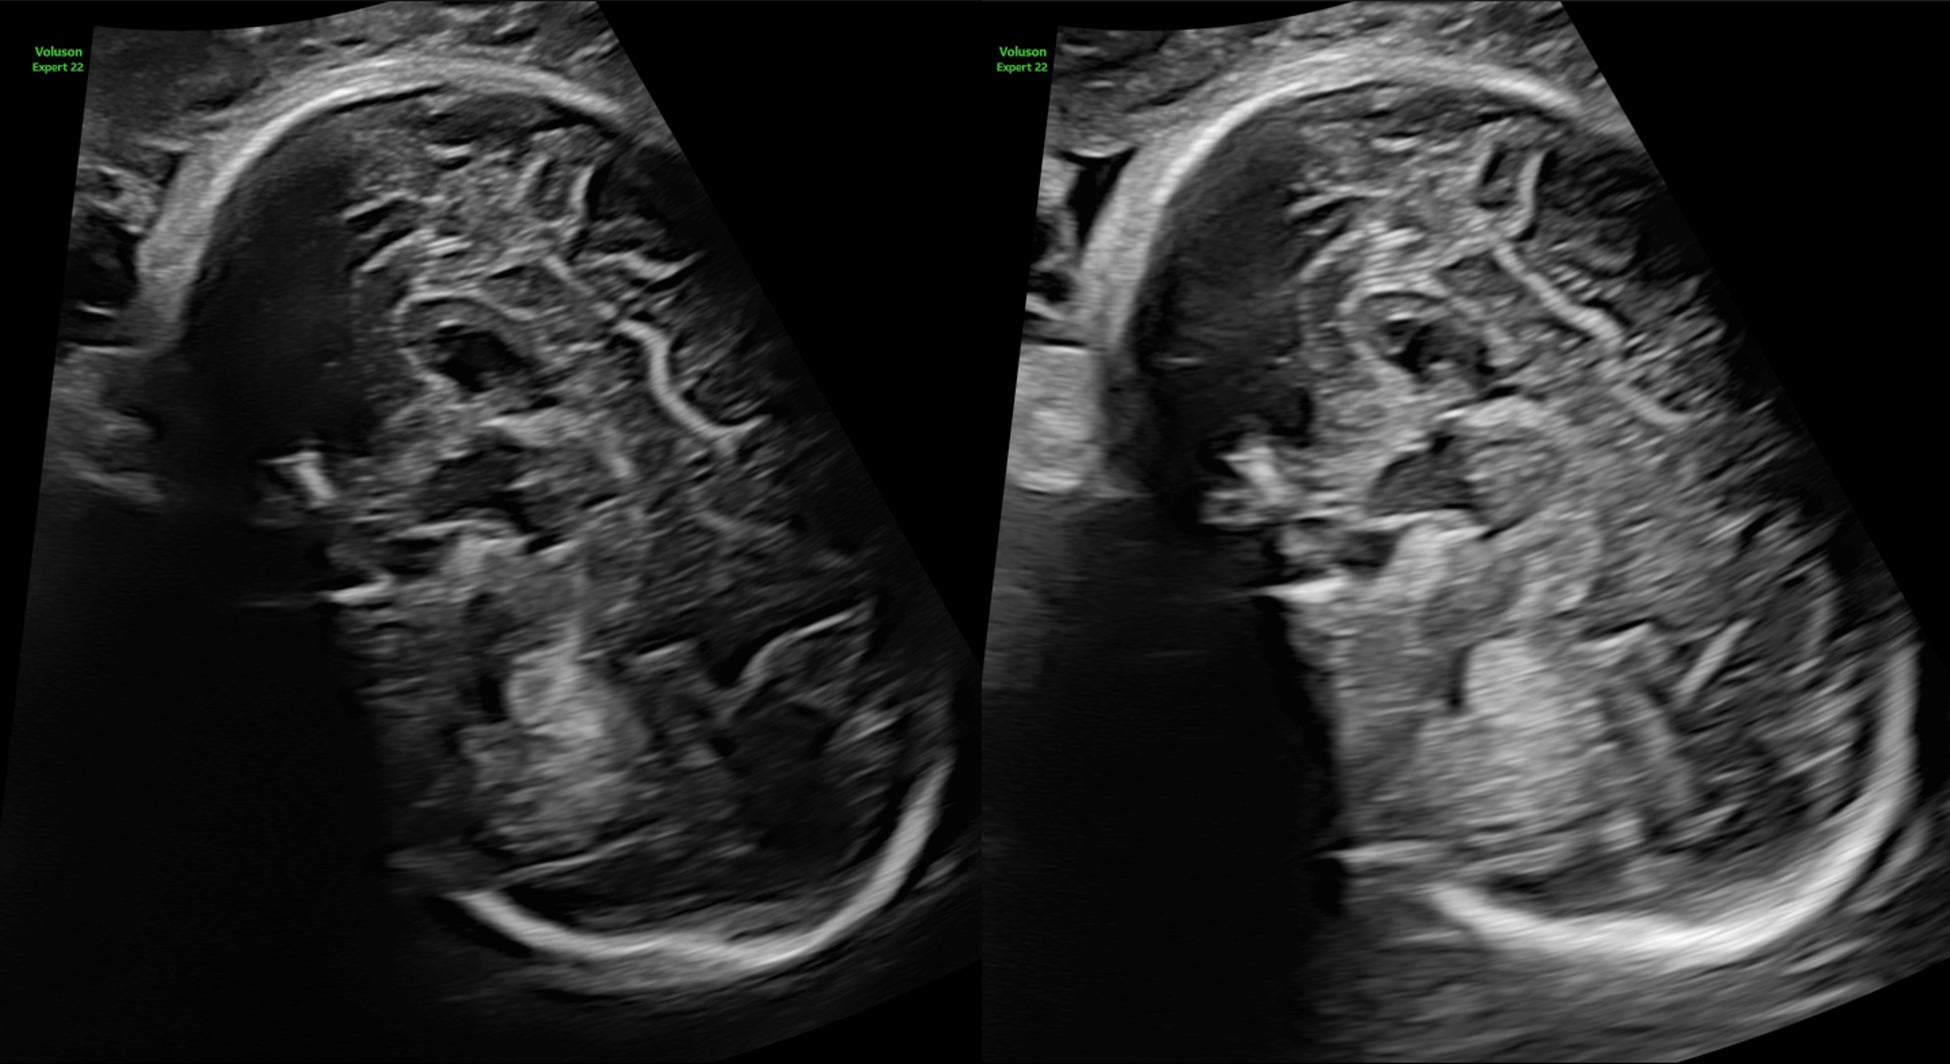

Voluson Expert 22では、より膨大な情報を高速処理可能な次世代エンジンLyric Architectureを搭載したことで、ソフトウェア制御されたビームフォーミングを実現。ハードウェア制御の限界を超え、格段に向上したペネトレーション、分解能、フレームレートを提供します。また、従来のVoluson製品では活用できなかった、新たなレベルの画像処理が可能となり、分解能に特化したイメージングモードから、深部感度に特化したイメージングモードまで、観察条件に大きく左右されることのない、明瞭な画像を提供します。

深部感度に特化したイメージングモード:Augment(Off/On比較)